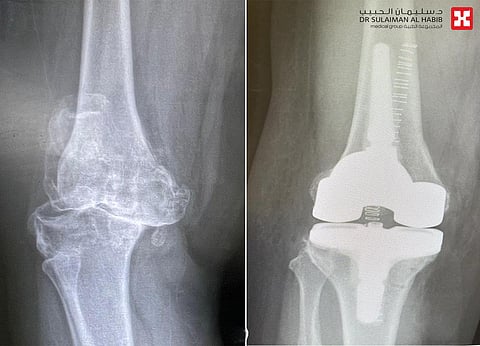

وأضاف د. سكيك أن الفريق الطبي أخضعها لفحوصات طبية دقيقة، بدأت بالفحص الطبي المبدئي، ومن ثم التصوير الإشعاعي الذي أكدت نتائجه، وجود خشونة حادة بمفصل الركبة، إضافة إلى تآكل الغضاريف والعظم المحيط بها، مع تأثر الأربطة وعدم الإتزان في المشي.

واستطرد د. سكيك قائلاً، أن المريضة أجريت لها عملية لاستبدال مفصل الركبة مع تركيب دعامات لتعويض الأربطة المصابة والعظم المتآكل بالساق، واستغرقت العملية "3" ساعات، ومضى التدخل الطبي الذي استخدم فيه الربوت الجراحي، كما رسم لها في الخطة العلاجية، وتكللت جهود الفريق الطبي ولله الحمد بالنجاح التام، حيث تمكنت المريضة من المشي في اليوم التالي، ولاحقاً زال الإنحناء واستعادت الركبة شكلها الطبيعي، كما أن المريضة تخلصت من الآلام وغيرها من الأعراض الحادة التي كانت تقض مضجعها، إضافة إلى أنها استعادت قدرتها الكاملة على الحركة، حيث غادرت المستشفى إلى منزلها مشياً على قدميها وبحالة صحية جيدة بعد "4" أيام من التنويم والعناية الطبية الحثيثة.